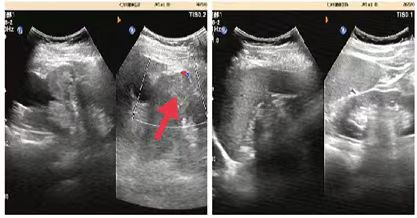

07**女士,65岁

2023年5月28日在邯郸仁泰北区体检,子宫附件彩超检查提示:子宫右上方见大小约8.9*7.4cm低回声团,内见范围约4.3*3.2cm液性暗区,CDFI:且见血流信号。考虑占位性病变,当日通知客户到三甲医院进一步检查,2023年6月10日跟踪回访,客户尚未检查,后连续三次跟踪客户均未检查,2023年8月1日又一次跟踪客户反馈已经检查考虑盆腔恶性肿瘤,家属还在纠结治疗方法,耐心讲解恶性肿瘤早期治疗的好处并劝说家属及时治疗,2023年9月1日再次回访,客户家属告知已完成手术,确诊为盆腔恶性肿瘤,并对仁泰体检专家对客户高度负责的状态表示感谢。